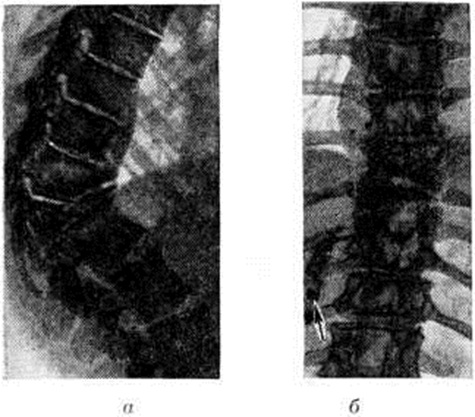

Возможны различные пути распространения туберкулёзного процесса из первичного очага через переднюю, заднюю и боковую поверхности тела позвонка (внедисковый путь), а также через межпозвоночный диск (внутридисковый путь). Процесс, распространяющийся внедисковым путем, приводит к обширным разрушениям позвонков. Прорываясь через переднюю поверхность тела позвонка, гной отслаивает переднюю продольную связку, распространяется под ней, образуя превертебральный абсцесс (рисунок 1, а), и вызывает контактное поражение других позвонков, так называемый поверхностную костоеду. Превертебральные абсцессы в зависимости от направления распространения гноя вызывают восходящий или нисходящий периостит (смотри полный свод знаний). При прорыве очага под заднюю продольную связку обычно возникают неврологический нарушения, обусловленные отёком спинного мозга (смотри полный свод знаний), сдавлением его гноем (рисунок 1, б), секвестрами, выступающими кзади остатками разрушенных позвонков, так называемый клином Урбана, утолщением мозговых оболочек вследствие пахименингита (смотри полный свод знаний). Характер неврологический нарушений определяется локализацией процесса и механизмом сдавления спинного мозга. При прорыве гноя через боковые поверхности тела позвонка образуются паравертебральные абсцессы, которые распространяются преимущественно в стороны от позвоночника и потому в меньшей степени контактно поражают тела соседних позвонков. В грудном отделе позвоночника такие абсцессы могут принимать форму веретена, полушарий, чечевицы, шаров, или так называемый ласточкиных гнезд (рисунок 2). В нижележащих отделах — нижнем грудном, поясничном и пояснично-крестцовом — абсцессы распространяются по мышцам, прикрепляющимся к пораженным позвонкам. Так, из поясничного отдела гной может распространяться в подвздошную область и далее — через мышечную лакуну на бедро. Из пояснично-крестцового отдела наиболее типичный путь распространения по ходу грушевидных мышц в ягодичную область. При внутридисковом пути процесс распространяется вертикально в направлении межпозвоночного диска, затем вовлекается студенистое ядро, а через него контактно — соседний позвонок (рисунок 1, в). Внутридисковое распространение гноя в большинстве случаев сочетается с малой деструкцией позвонков и наклонностью к отграничению процесса.

Во многих случаях при туберкулёзном Спондилит натечные абсцессы могут быть диагностированы рентгенологически. В шейном отделе позвоночника абсцесс распознается по дугообразному выпячиванию задней стенки трахеи и глотки. В грудном отделе тень абсцесса на фоне лёгочных полей довольно отчётливо дифференцируется и имеет форму веретена, луковицы и так далее Очертания абсцесса гладкие и чёткие (рисунок 5). Для уточнения объёма и распространённости абсцесса применяют абсцессографию (рентгенологические исследование после заполнения опорожненной полости абсцесса контрастным веществом), а при наличии свища — фистулографию (смотри полный свод знаний). В поясничном отделе абсцессы диагностируются по косвенным признакам — выпячиванию наружного края большой поясничной мышцы.